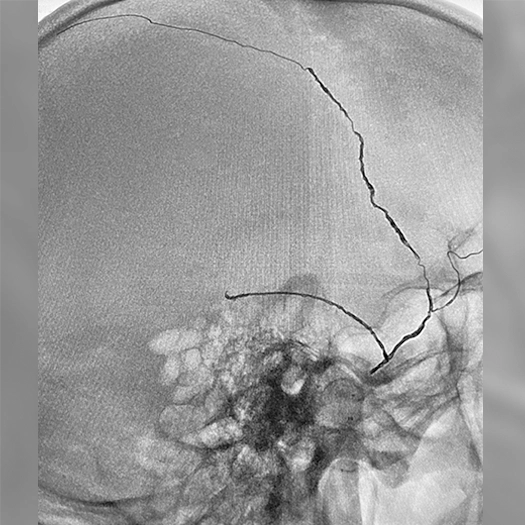

angiogram of embolization coils in a vessel

MMA embolization with 3 SwiftPAC coils: 45 cm, 15 cm, 30 cm

MMA Embolization

• SwiftPAC coils offered embolization

• MIDWAY 43 provided delivery support

• BENCHMARK071 provided stable, reliable access

• A combo designed to support confident, controlled delivery (see case to left)